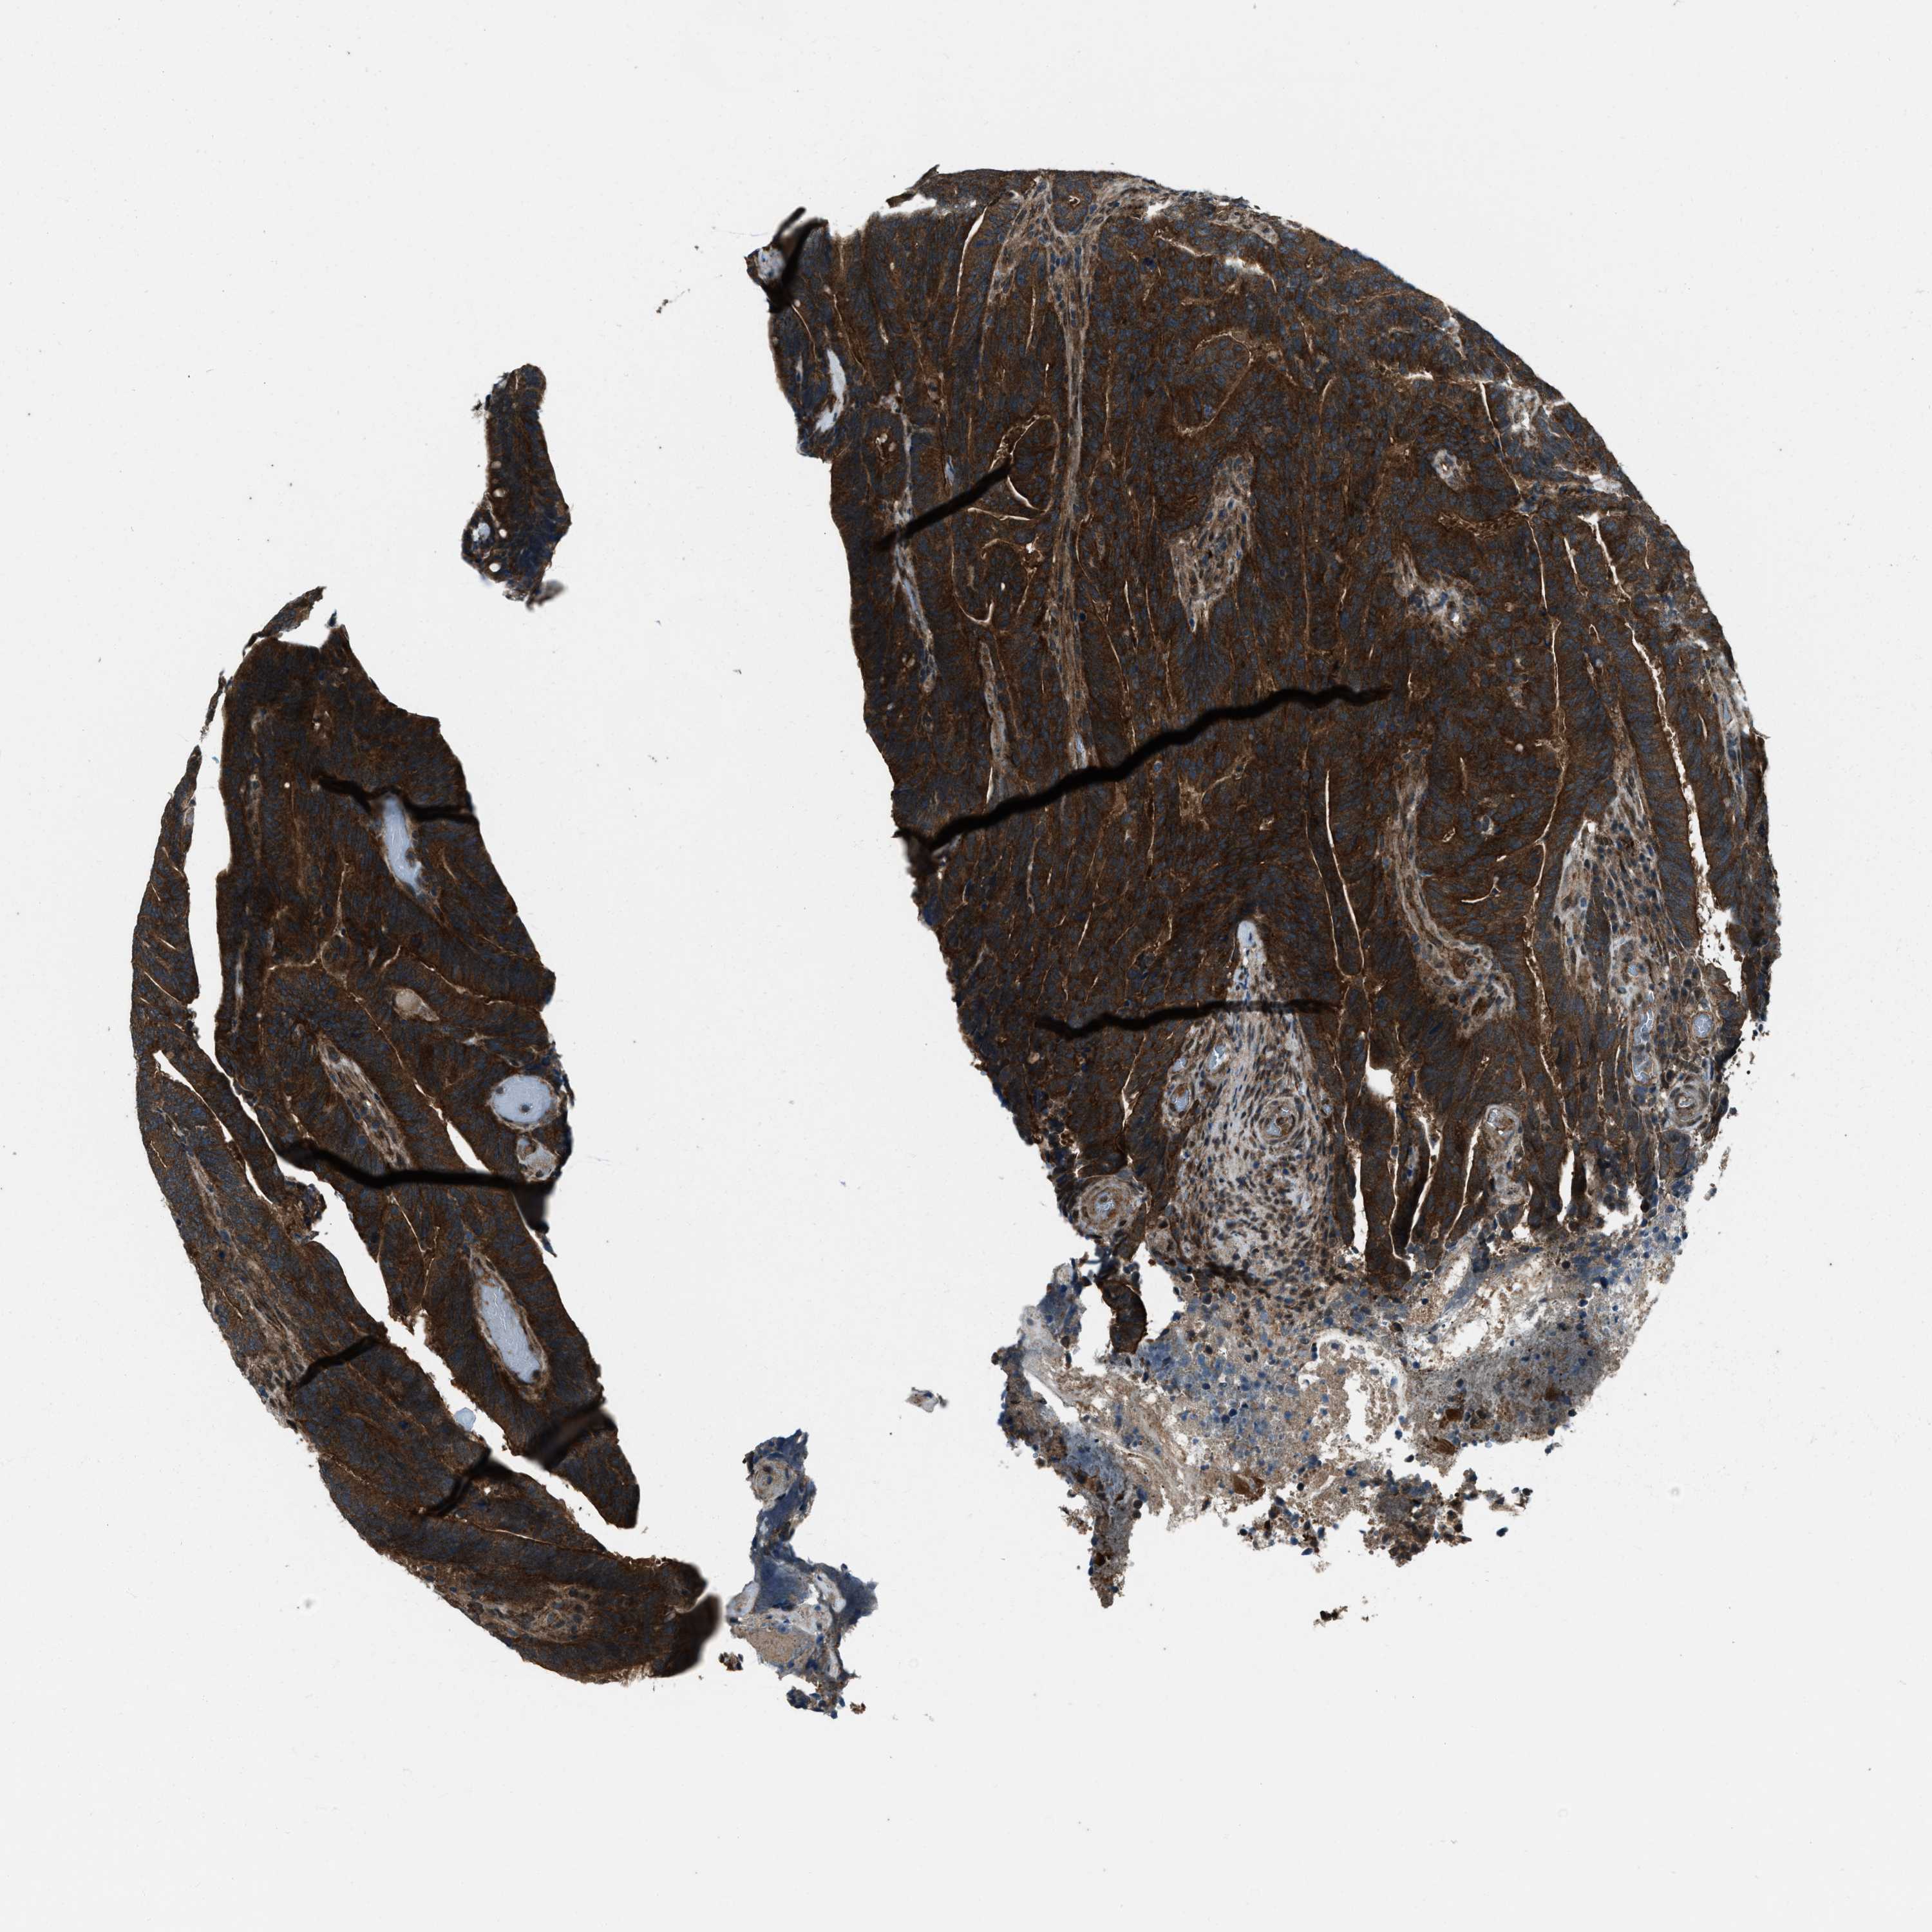

Colorectal cancer

Human cancer

Colon adenocarcinoma

Rectum adenocarcinoma